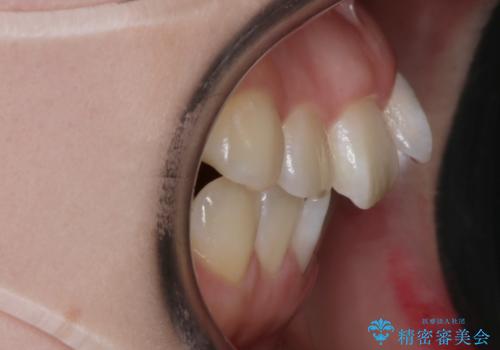

- 前歯のガタつきと口元の改善を主訴に来院されました。

なるべく目立たない装置が良いというご要望と、口元を引っ込めたいというご要望を両方達成するために今回はハーフリンガル装置を選択し治療計画の立案を行いました。

結果的に表の装置よりは期間が掛かりましたが、口元もしっかり下がり韓国美人な横顔になったと患者様にも喜んでいただけました。